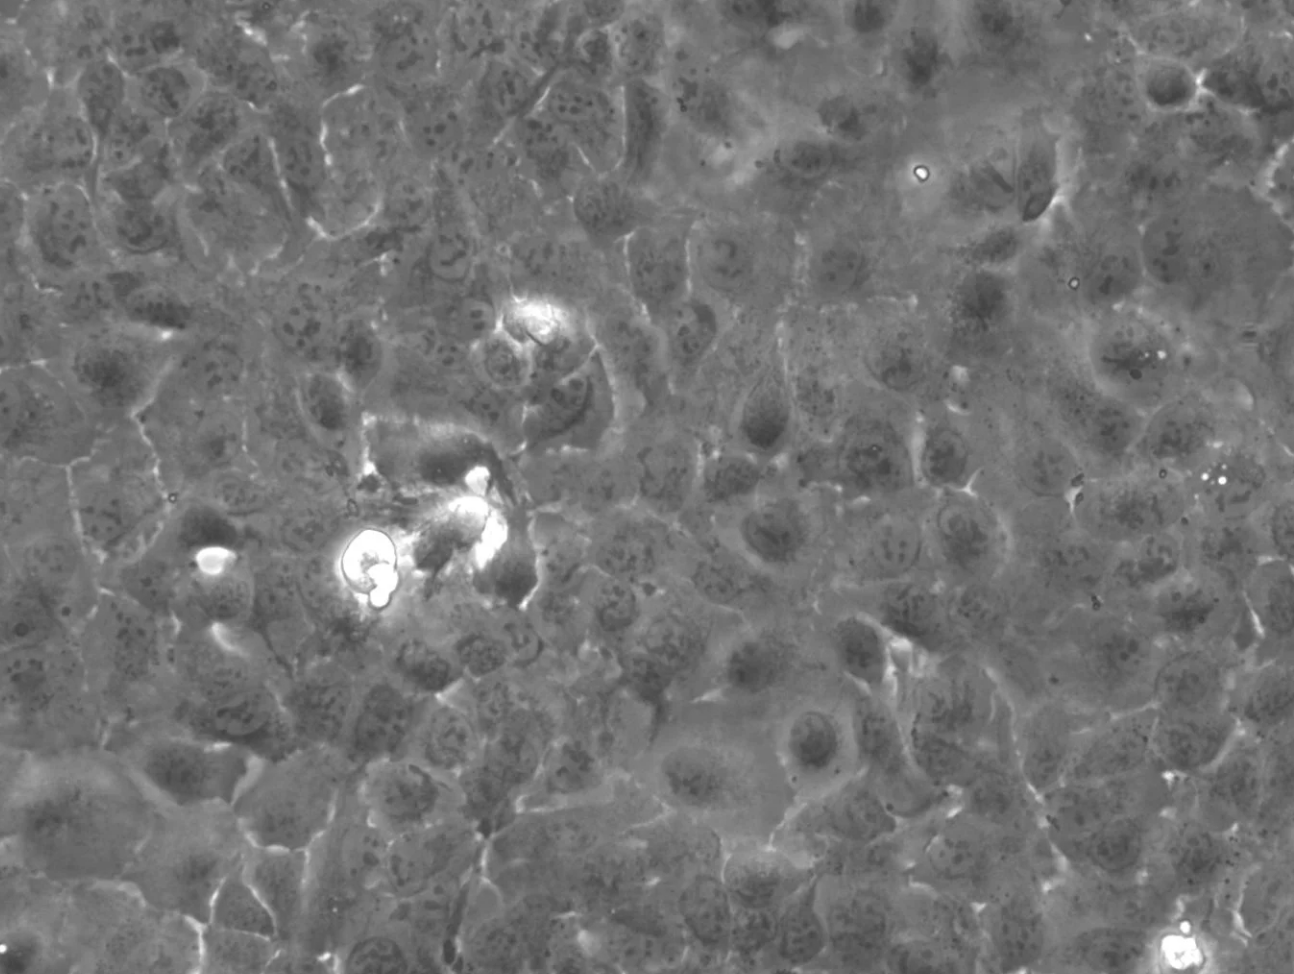

形態(tài)

上皮細(xì)胞樣

生長(zhǎng)特征

貼壁生長(zhǎng)